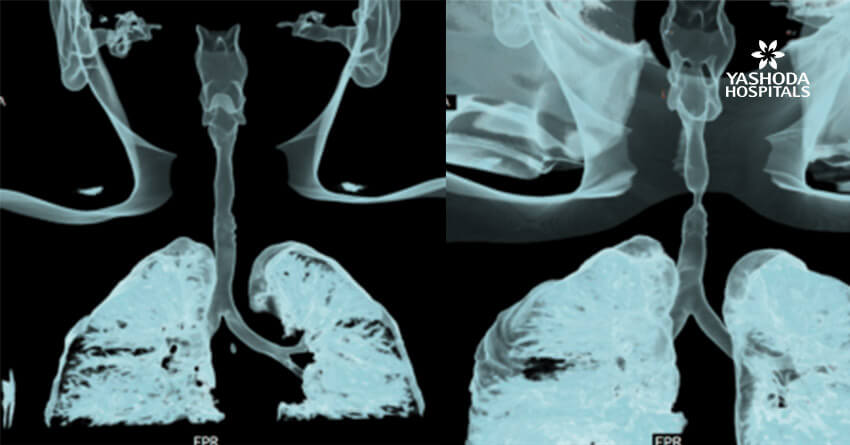

A 6-year-old female child presented to our clinic with progressive breathlessness and stridor for a duration of 5 days. She had a recent history of road traffic accident and sustained head injury and underwent craniotomy for extradural hemorrhage. Post-surgery she was on mechanical ventilator support for 10 days after which she was extubated. She developed stridor after 7 days of extubation. CT Neck revealed focal hour-glass configuration, concentric asymmetrical subglottic narrowing with associated soft tissue thickening 2-3cm below the level of vocal cords, with a diameter of 4.5 x 5.0 mm (AP X TR) at the point of maximal narrowing. Diagnostic flexible bronchoscopy showed circumferential stenosis (Grade III Myers-Cotton) of subglottic area about 2.5 cms below the glottis and we could not negotiate beyond the level of stenosis.

Rigid bronchoscopic repair of the stenosis was performed combining serial rigid bronchoscopic dilatations and balloon bronchoplasty using CRE dilatation balloons of varying sizes. Post dilatation, we were able to negotiate the rigid bronchoscope beyond the level of stenosis and were able to achieve a lumen of 100% with no residual stenosis. Follow-up CT Neck showed normal caliber of tracheal lumen with a luminal diameter of 8.6 x 8.3 mm at the level of previous narrowing. Total reduction of the clinical stridor was observed post procedure. Surveillance bronchoscopy after 4 weeks showed no further narrowing and good patency of tracheal lumen. Patient remained asymptomatic in subsequent follow up visits with improved pulmonary function tests

Radiology Images: